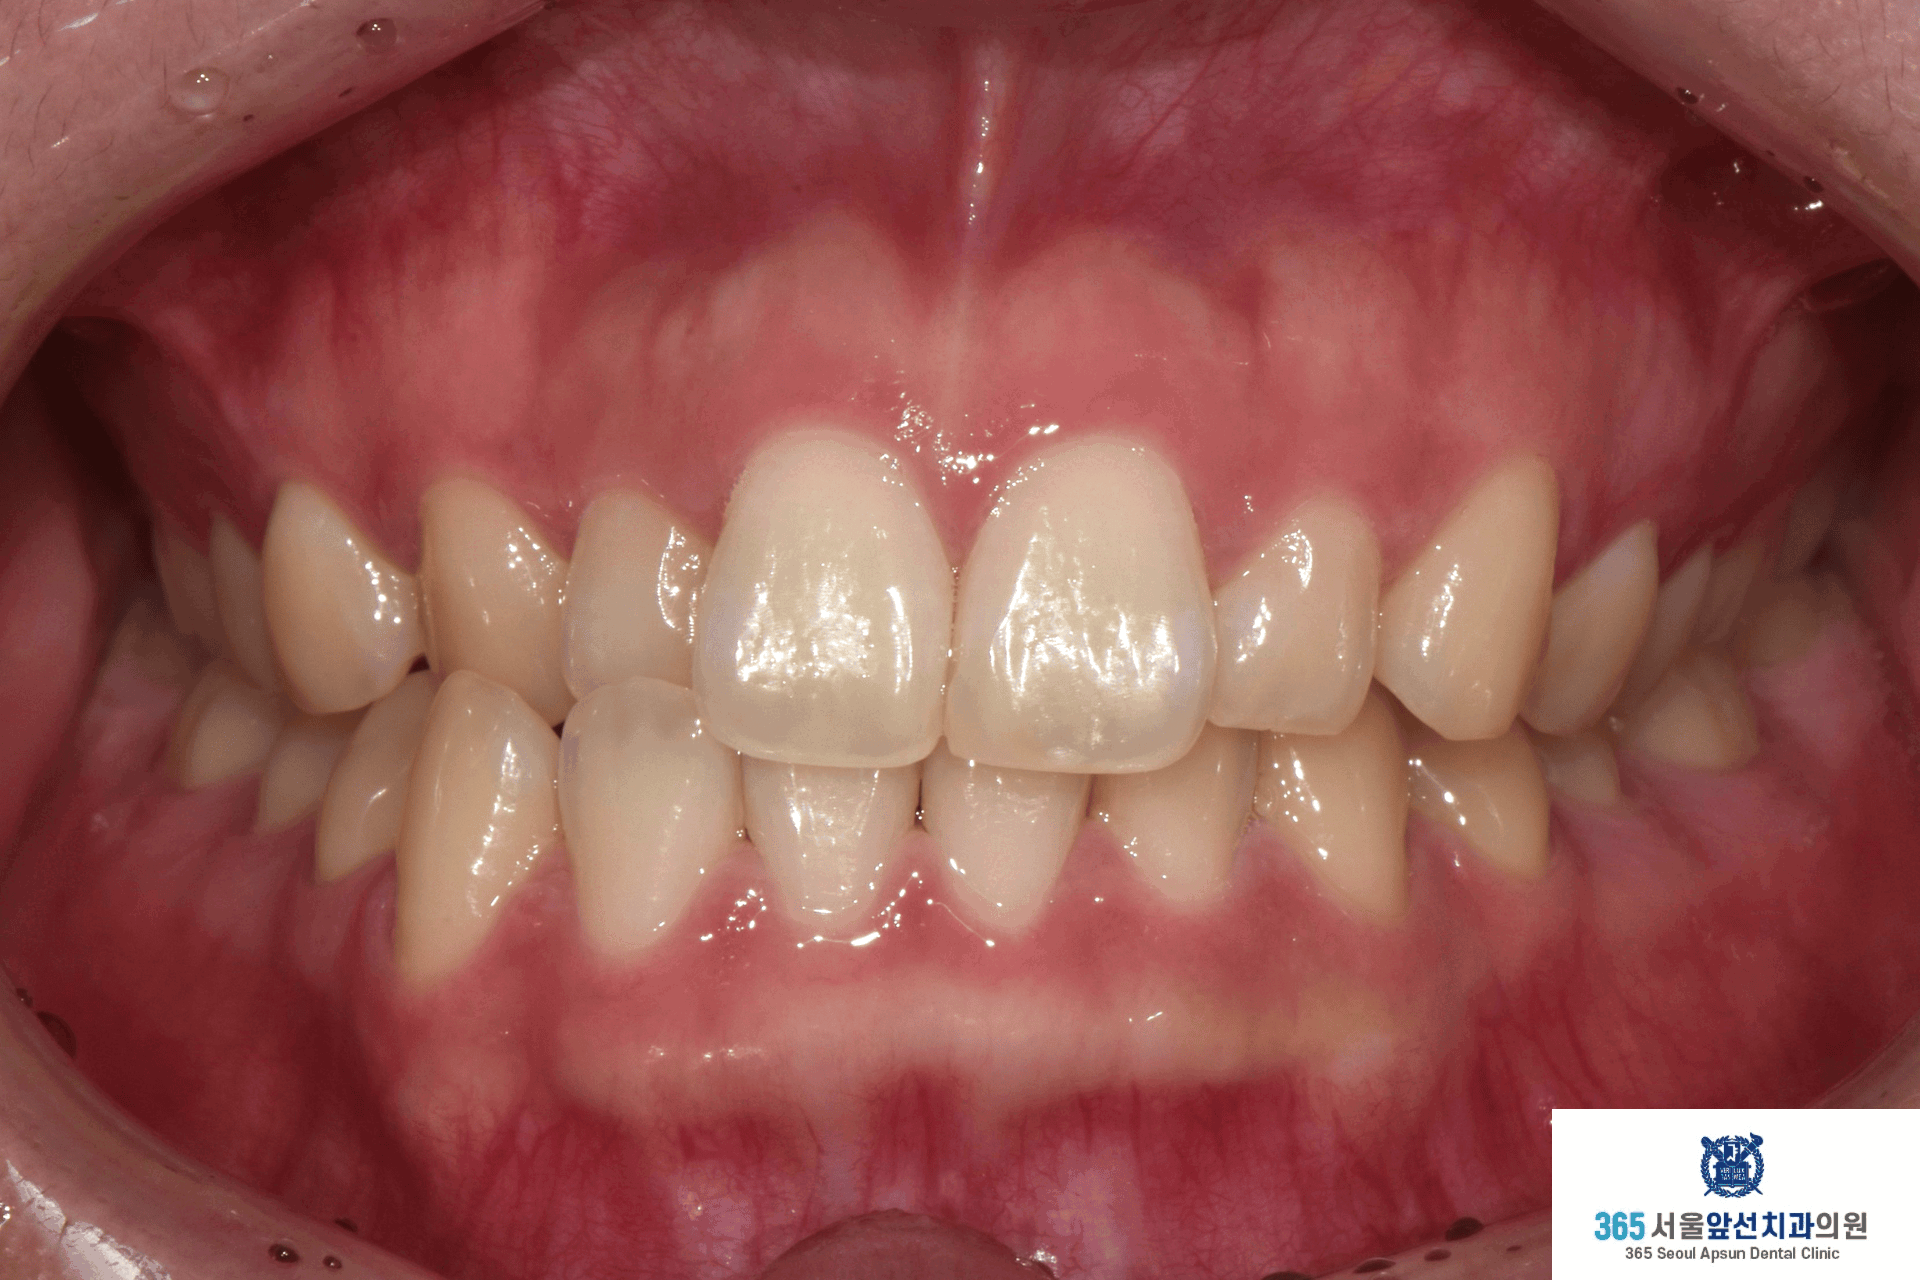

촬영일시 : 2024.10.23. / 2025.11.12. 반대로 물리는 이 때문에 입술이 비틀어져 보인다는 고민으로 내원하신, 성장이 완료된 10대 청소년 환자 분의 증례를 소개드리겠습니다.

촬영일시 : 2024.10.23. 치료 전, 우측 측절치와 견치(송곳니)의 반대교합과 정중선 불일치가 관찰됩니다. 양측 상악 측절치가 5.6mm 폭경으로 왜소치 경향을 보이며 Bolton 의 전치부 비율이 86.73으로, 이상적인 윗니와 아랫니 앞니의 비율을 고려한 폭경에 비해 5.0mm가 부족합니다. 이 경우, 왜소치의 폭경을 키워 수복한다면 이상적인 교합을 형성할 수 있습니다. 해당 환자분께서는 왜소치의 수복 없이 치료하기를 원하셔서, 보상적으로 하악 치열의 폭경 감소와 Canine key compromise를 통해 최대한 심미적이고 기능적인 교합을 만들어드렸습니다.